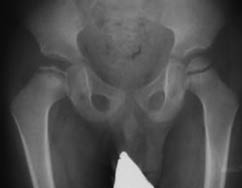

The pathogenesis of Perthes disease has not yet been fully studied. It is gratifying that over the past decade, there have been more and more scientific studies devoted to the pathogenesis of Perthes disease since the key to the success of adequate treatment of such complex orthopedic pathology is elucidating the mechanism of osteonecrosis. Some authors believe that the disorder (delay) of endostosis combined with the constitutional predisposition toward growth retardation leads to a decrease in the mechanical strength of the femoral head in patients with Perthes disease [1–4]. The disease is associated with improper differentiation of bone tissue by the controlling gene COL2A1. Its primary mutation triggers a cascade of pathological reactions that cause collagen formation disorder in the form of intratissual anomalies (markers of connective tissue dysplasia) in various organs, systems, and anatomical and topographical regions of an individual [5–7]. Osteonecrosis is caused by impaired intercellular interaction (osteoblast (osteocyte) – osteoclast) toward activation of osteoclasts [8]. Other researchers say that it occurs along with vascular pathology in boys with a hypersthenic constitution during a period of active growth. Lack of blood flow results in anemic infarct of the affected epiphysis of the femur [9–11]. Another possible scenario for the development of osteonecrosis is congenital maldevelopment of the spinal cord in the lumbar region (myelodysplasia). Disorder of the innervation of the hip joint (HJ) changes the size and number of vessels, as a result of which the blood flow in the HJ tissues is chronically reduced and the tissues are undernourished [12, 13]. At stage II of Perthes disease, the proximal epiphysis of the femur decreases in size, whereas at stage III, it is partially or completely subjected to resorption. At stage IV, the proximal epiphysis is partially restored. Subsequently, multiplanar deformities of the proximal femur are formed (Figures 1, 2).

Fig. 1. X-ray of the hip joint in the anteroposterior projection of the patient T., 4 years. Diagnosis: "Perthes disease on the right, stage II", when Catteral II arrives